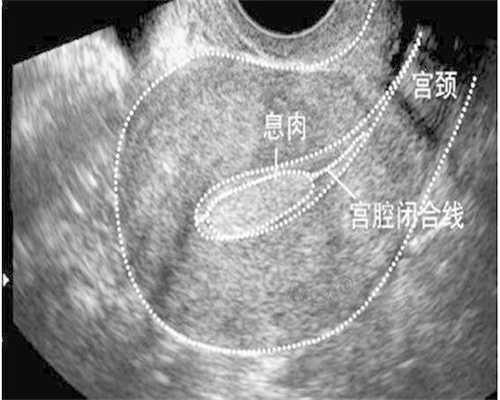

在三代代生孩子双胞胎过程中,还需要进行多次监测和检查,以确保胚胎顺利发育。这些检查通常包括血液检验、超声波检查等。每次监测和检查的费用大约为500-1000美元。